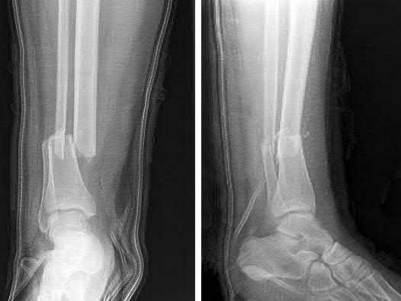

A 28-year-old male sustains a severe hyper-dorsiflexion injury to his ankle in a motor vehicle accident, resulting in a Hawkins Type III talar neck fracture. Which of the following arteries provides the predominant blood supply to the body of the talus, placing it at significant risk for avascular necrosis in this injury?

The artery of the tarsal canal, which is a branch of the posterior tibial artery, provides the dominant blood supply to the talar body. In a Hawkins Type III fracture (talar neck fracture with subtalar and tibiotalar dislocation), the blood supply from the artery of the tarsal canal, the artery of the sinus tarsi, and capsular vessels are disrupted, leading to an avascular necrosis (AVN) rate approaching 100%.